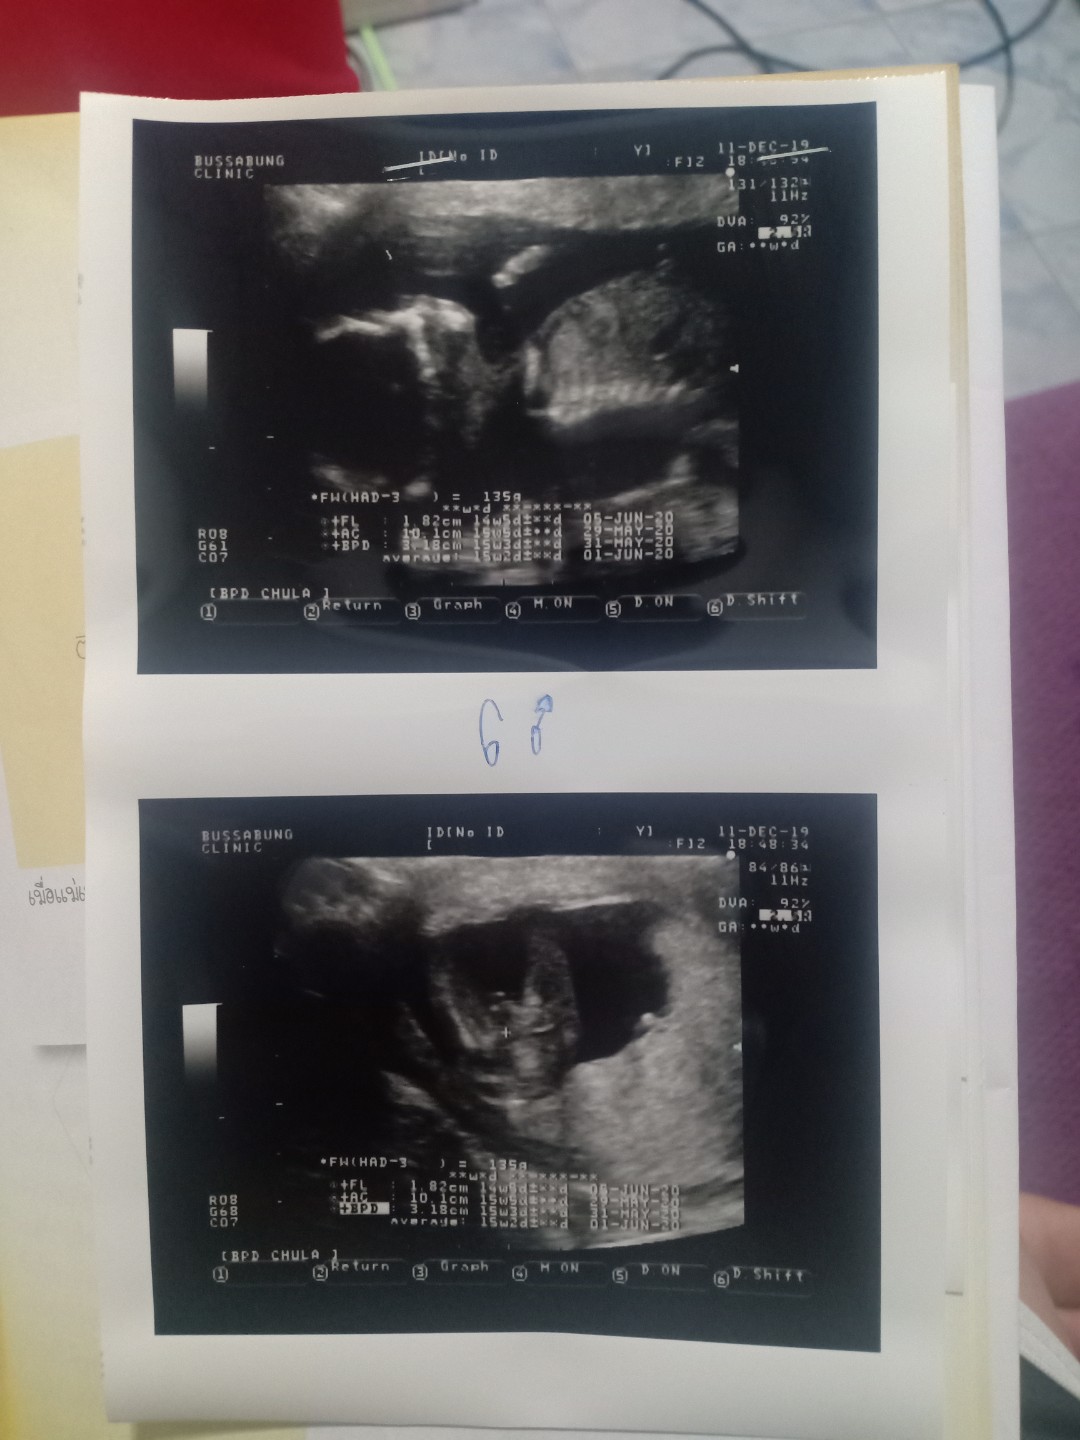

ผุ้ชายจ้า